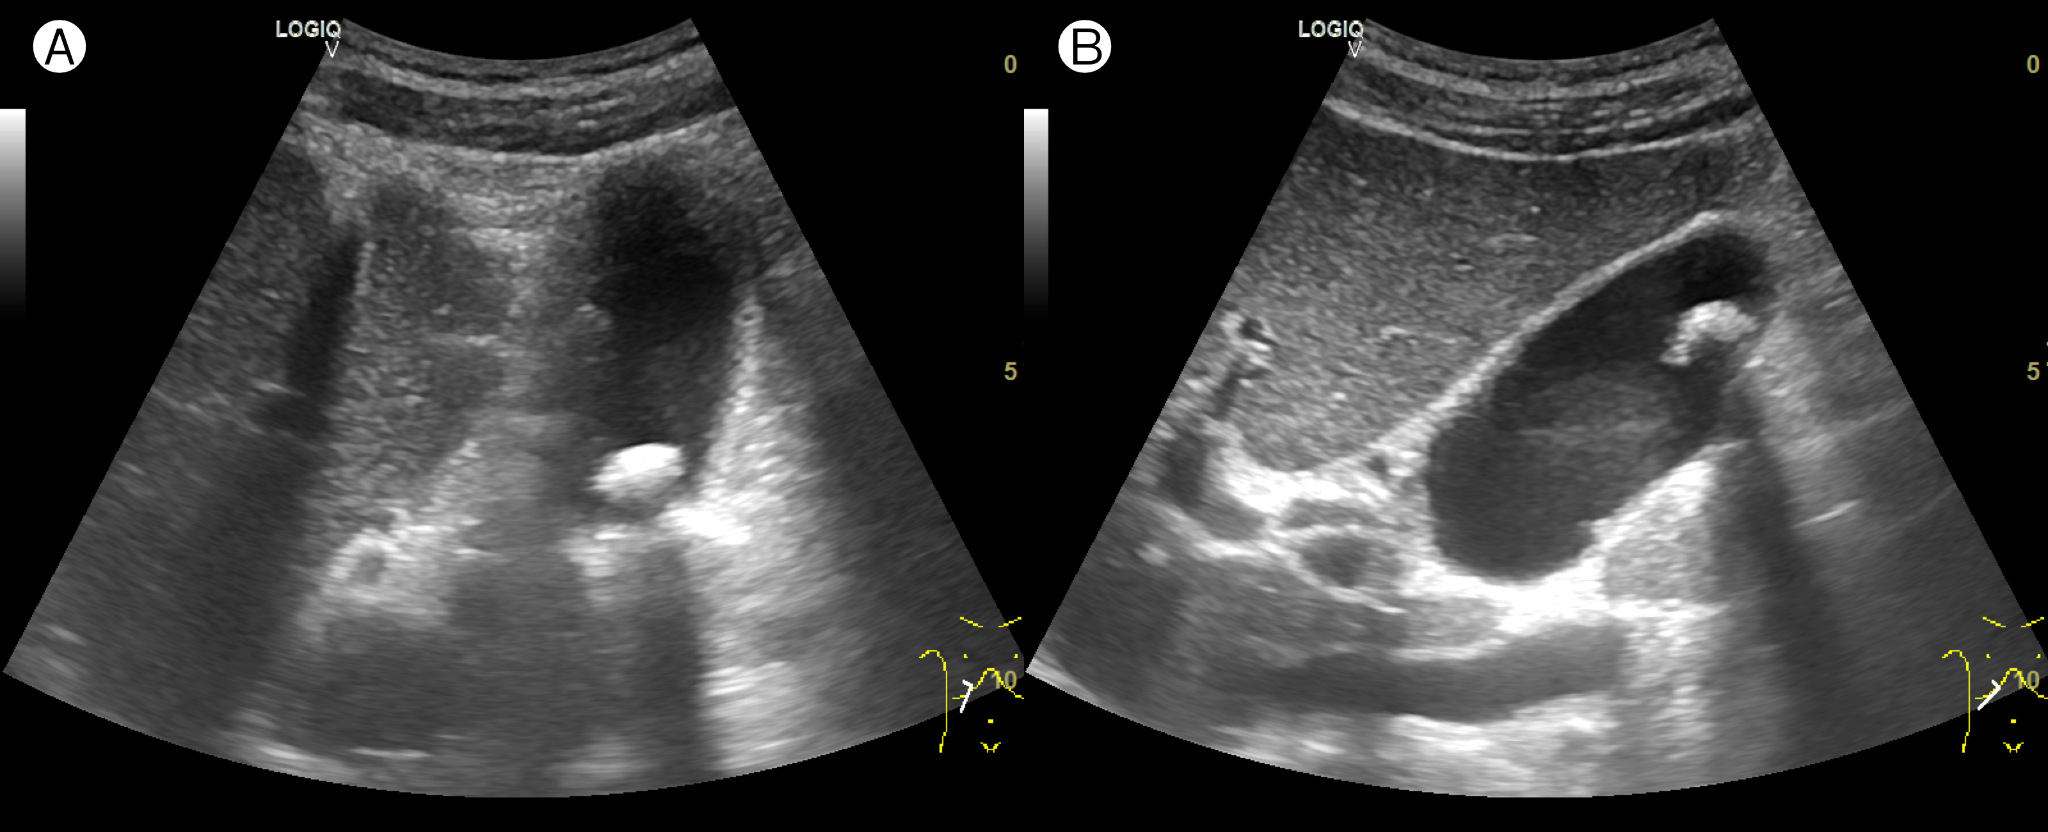

상복부 초음파 검사 결과, 보이는 췌장 부분에서는 특이 소견이 관찰되지 않았다. 하지만 담낭 내부에서 후방음영을 동반한 고에코 소견이 관찰되었고, 이는 체위 변화에 따라 움직이는 양상을 보여 담낭결석으로 판단됐다(그림 1).

그림 1. 당뇨병 환자(관해 상태)의 상복부 초음파 검사 ― 담낭결석(cholelithiasis); (A) 바로 누운 자세(supine position); (B) 바로 앉은 자세(upright seated position)